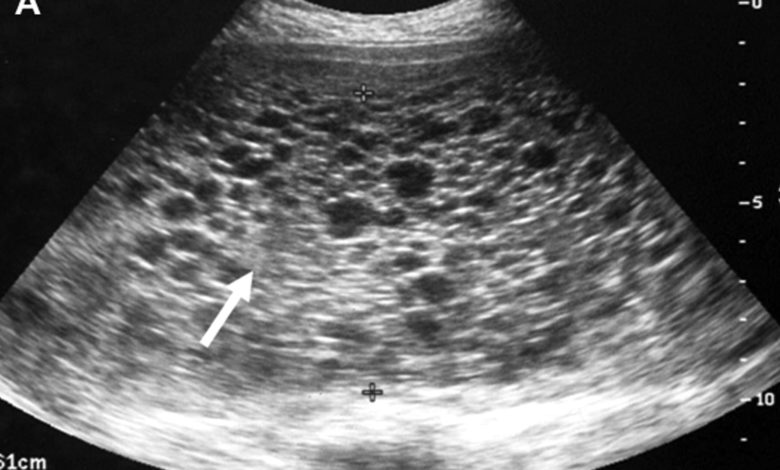

Hastanın şikayetlerinin dinlenmesi ve muaynesi sonrasında veriler değerlendirilir. Hasta ultrasonografik incelemeye tabi tutulur.Ultrasonda rahimiçinde çoklu ekoların oluşturduğu tipik kar fırtınası görünümü gözlenir.Ayrıca kanda gebelik haftasına göre aşırı artmış Beta HCG tanıyı destekler.